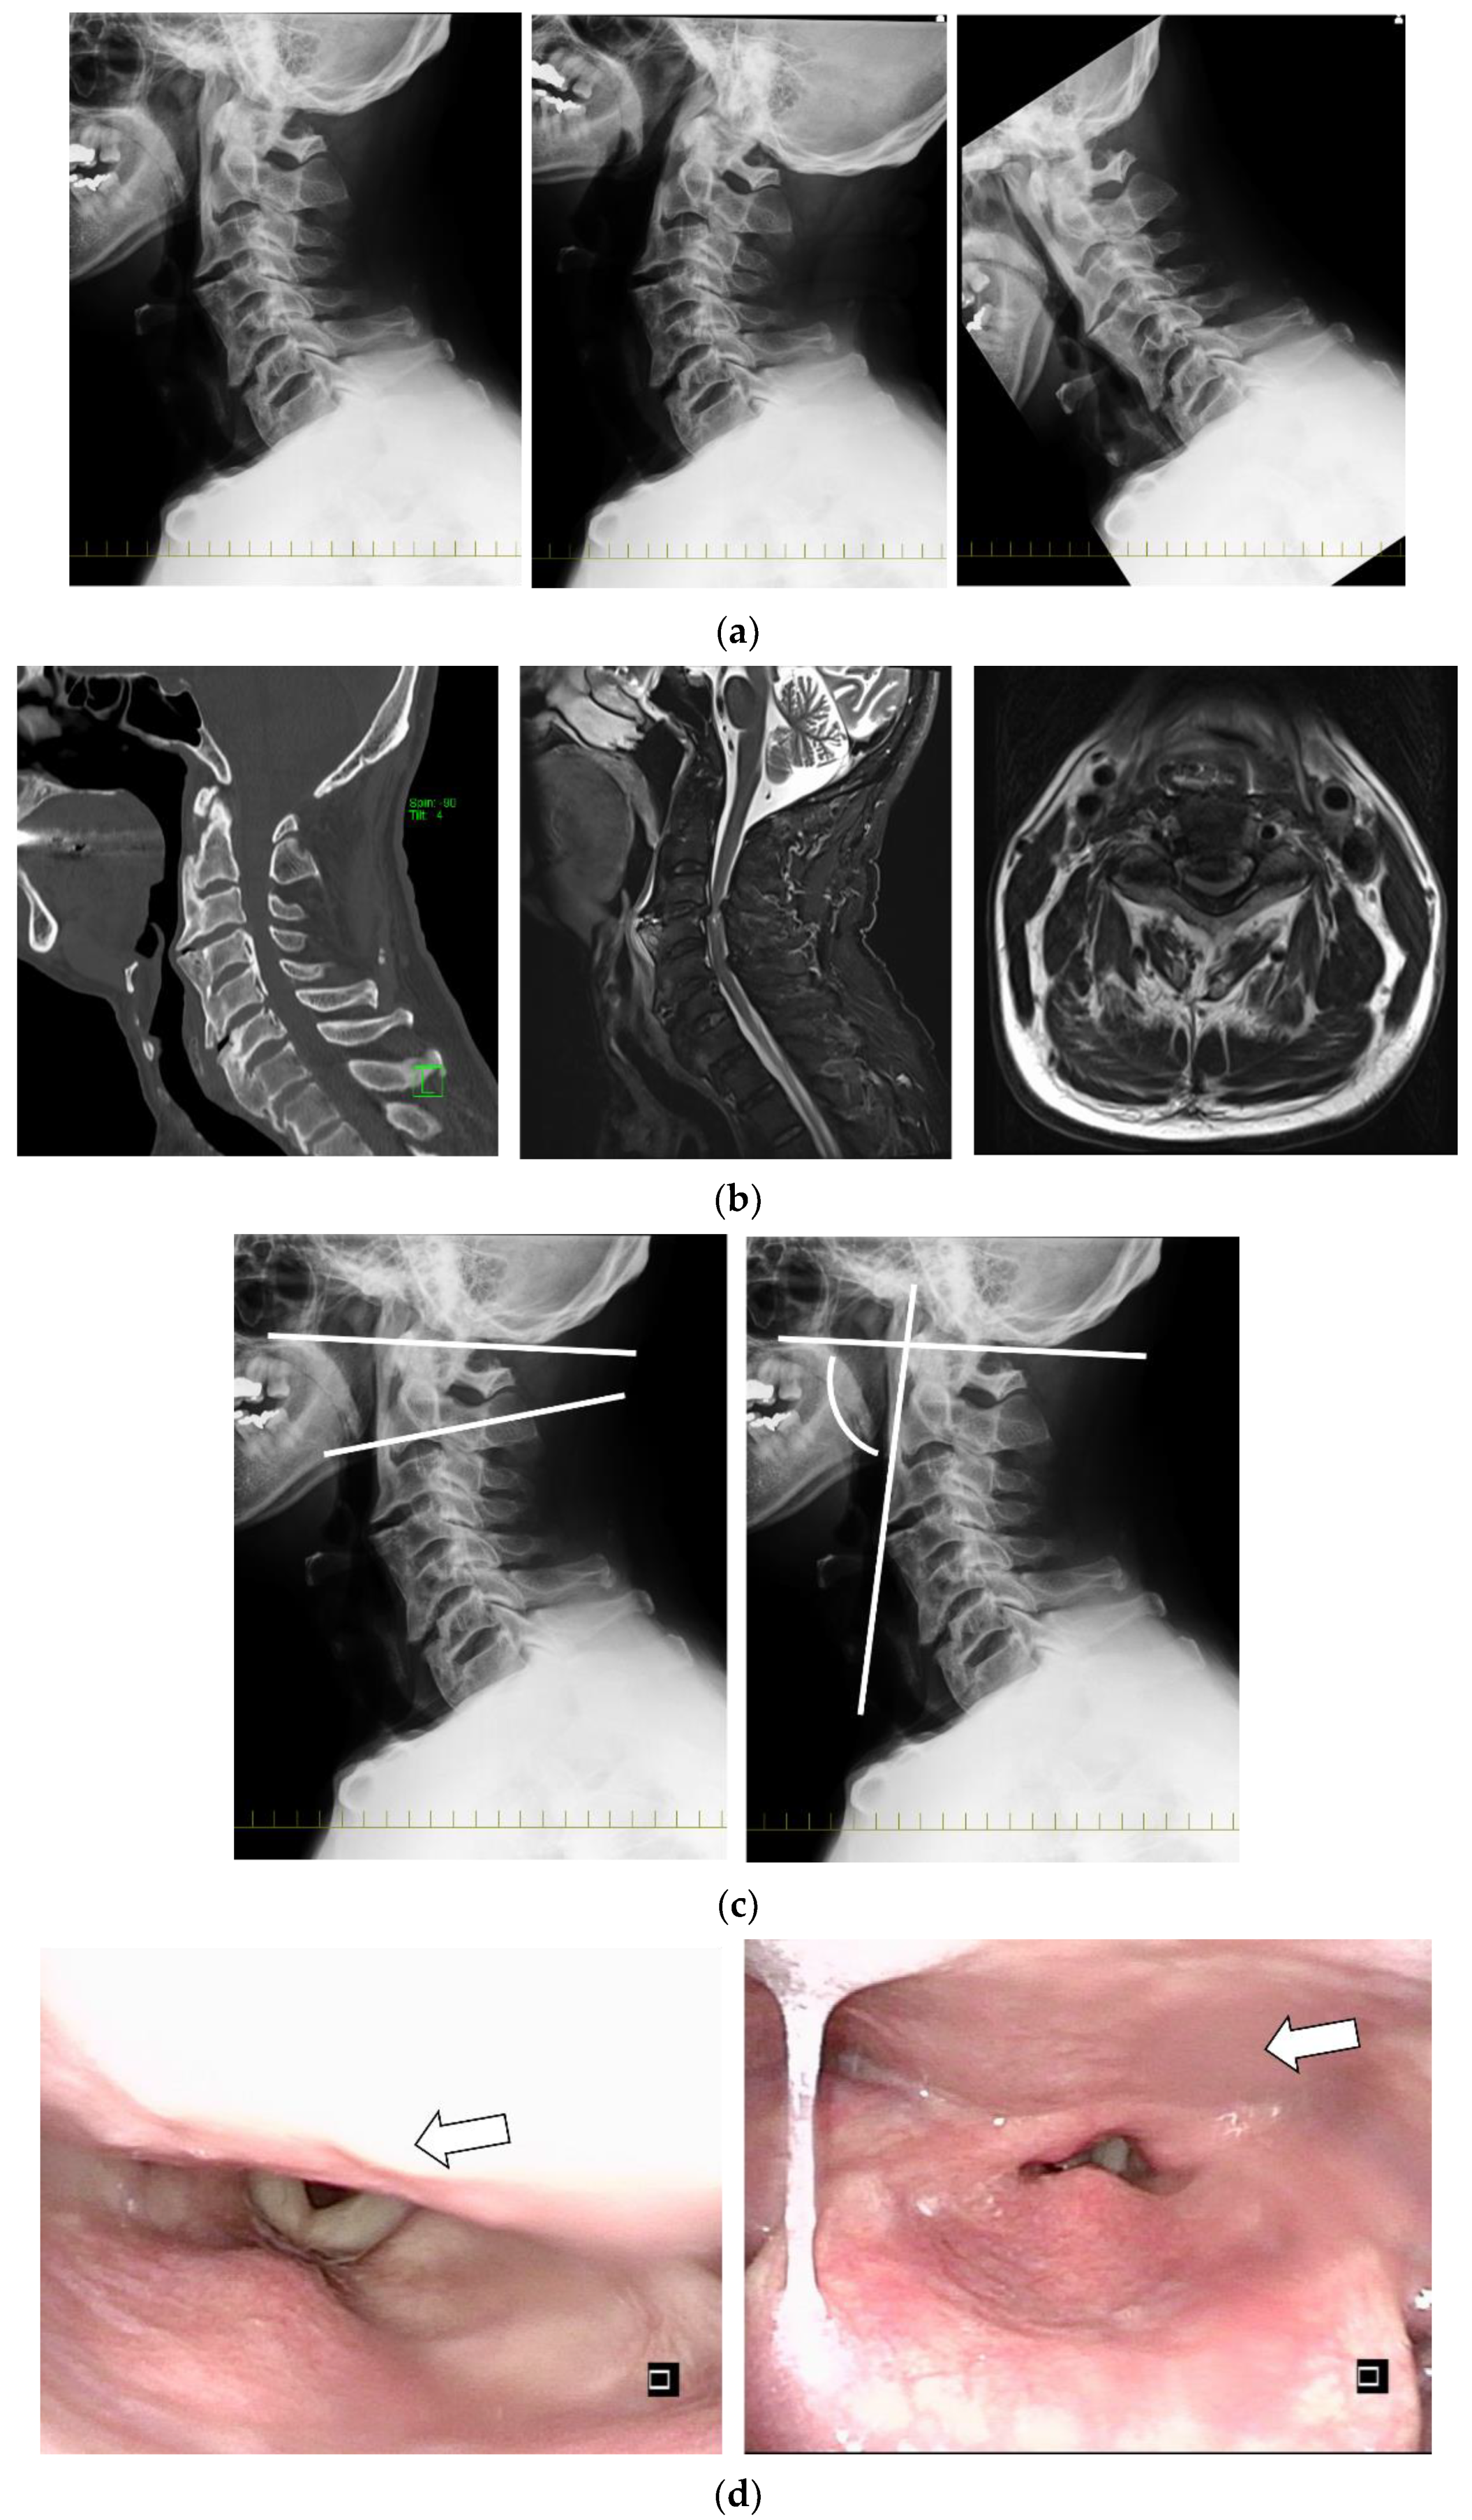

2.5. Clinical Presentations